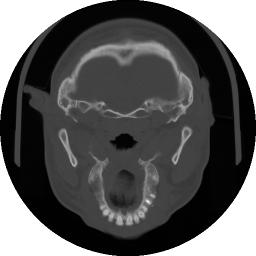

Figura 12 Immagine TAC relativa ad una sezione trasversale del cranio.